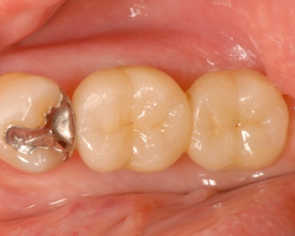

インプラント治療例

ケース①(新宿区在住 50代 女性)

ケース②(新宿区在住 70代 女性)